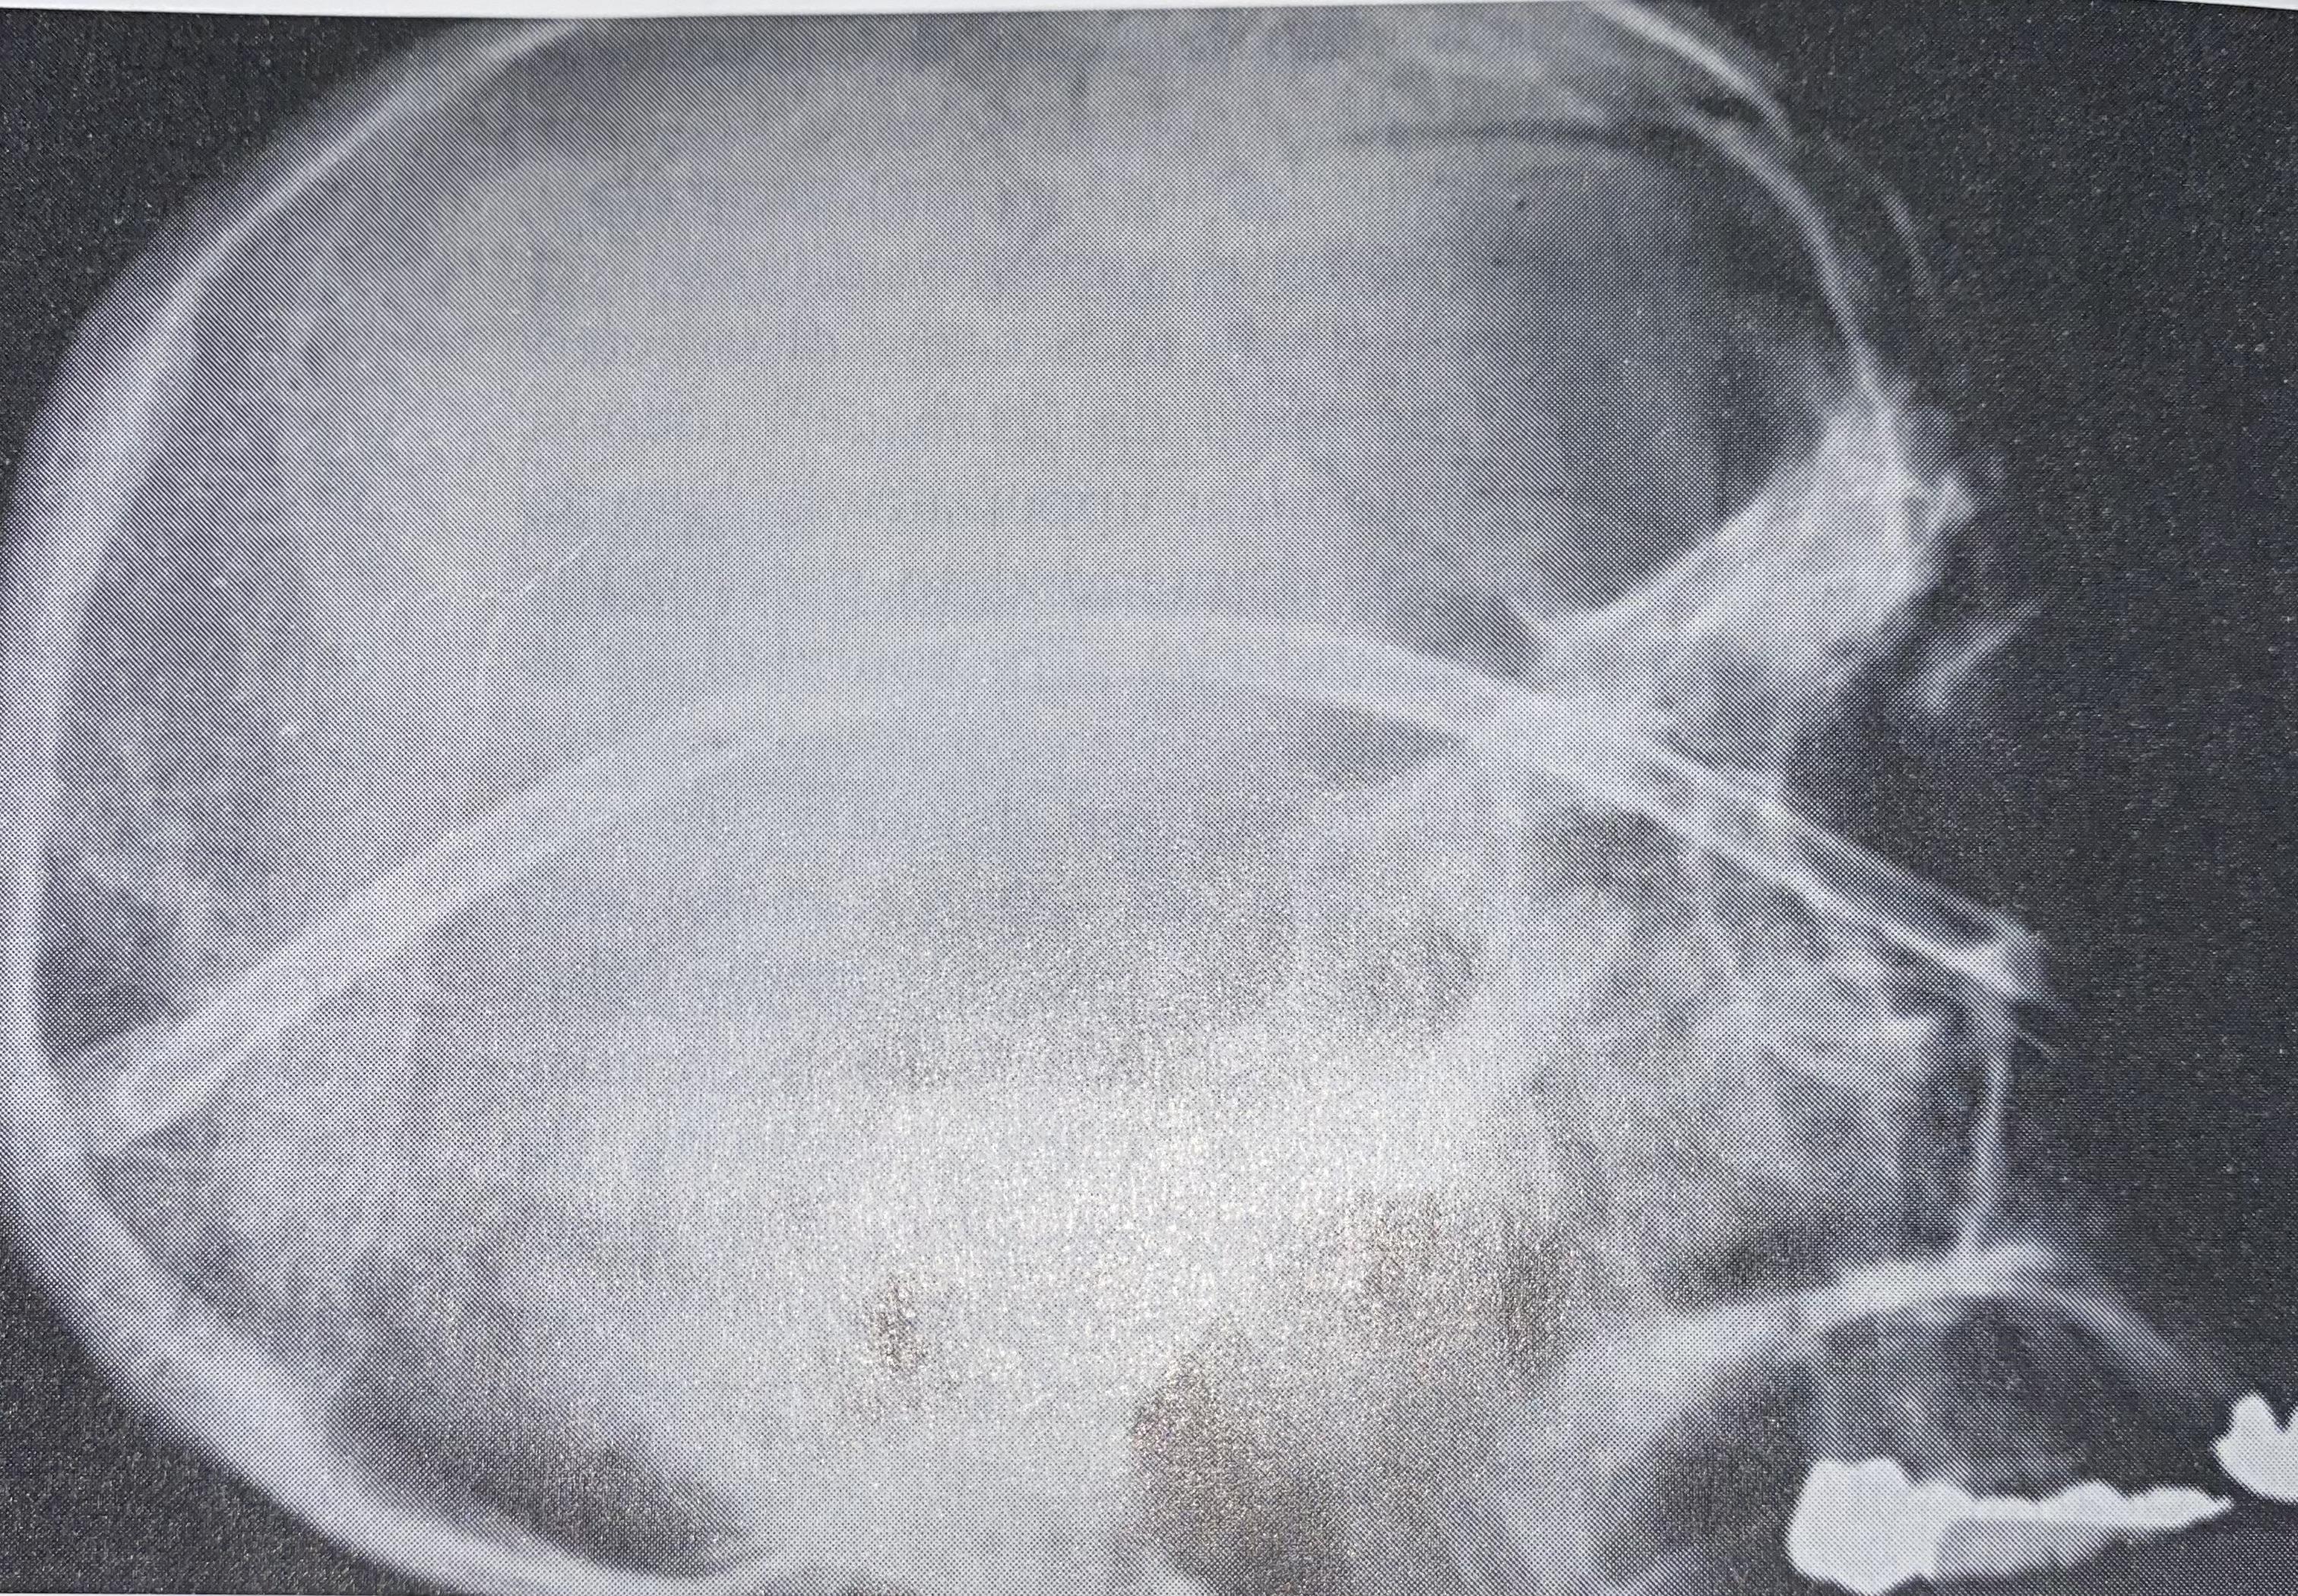

From ctscannerinfo.blogspot.com

Computed Tomography May 2015 How Much Water Do I Drink Before A Ct Scan Of water or clear juice. Don't eat or drink anything for 3 to 4 hours before your scan. if you are having a ct scan of your abdomen or pelvis, you may be required to drink an oral contrast solution or water before your. You may have clear liquids up to two hours before the examination. If you need. How Much Water Do I Drink Before A Ct Scan.